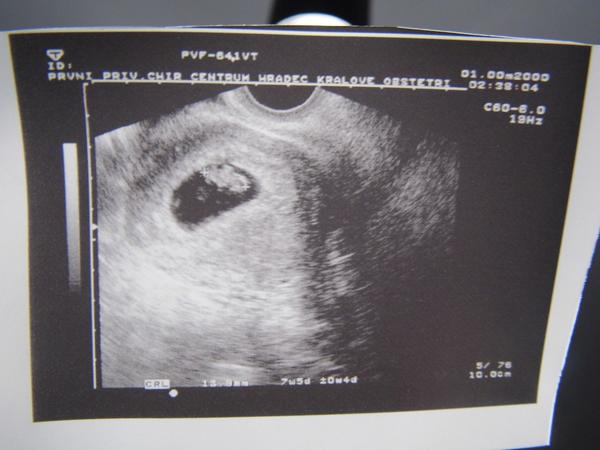

Ahoj holky, tak dnes se se mnou rozloučili v Caru a v pondělí jdu na kontrolu již k Dr. Vše v pohodě, prcek má necelý 1,5cm, ale hematom se zvětšil, takže fakt nohy hore a odpočívat. Tady máte zase ukázku toho šmudly našeho 😀